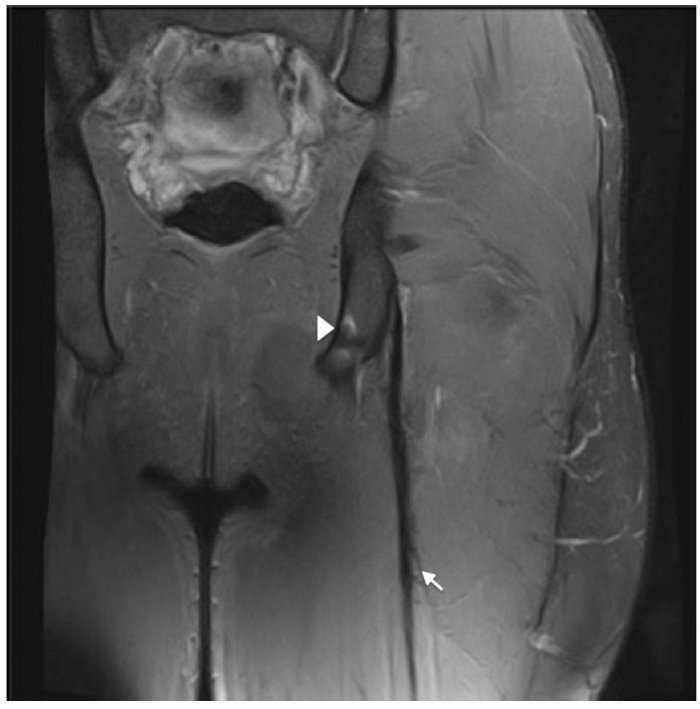

Un jugador de futbol professional de divuit anys sofrí el mateix tipus de dolor en les mateixes circumstàncies. Els senyals clínics eren totalment similars als del cas dels isquiotibials aguts descrit, però la prova d’RM mostrà imatges diferents (figs. 3 i 4) perquè la lesió estava localitzada al tendó lliure del bíceps femoral. La longitud del tendó lliure fou 8,5 cm i la lesió fou localitzada a 6,5 cm de la tuberositat isquiàtica. Degut al llarg període de recuperació i a un índex elevat de relesió, cal considerar el tractament quirúrgic. Es realitzà l’escissió del teixit cicatricial, incloent-hi el trencament parcial del tendó y la sutura sense tensió del romanent del ventre del bíceps femoral al semitendinós adjacent, amb la finalitat de proporcionar tensió al tendó i reforç amb ancoratge a la tuberositat isquiàtica (figs. 3 i 4).

Figura 2 Les imatges coronal i axial en T2 amb supressió de greix de l’isquiotibial esquerre mostren canvis de gruix i intensitat del senyal del tendó lliure (fletxa), contorns borrosos i discontinuïtat ampliada fins a UMT proximal. Existeix retracció distal lleu d’UMT proximal. Ventre del múscul semitendinós (ST), gluti major (GM), tendó semimembranós (punta de fletxa) i nervi ciàtic (*).